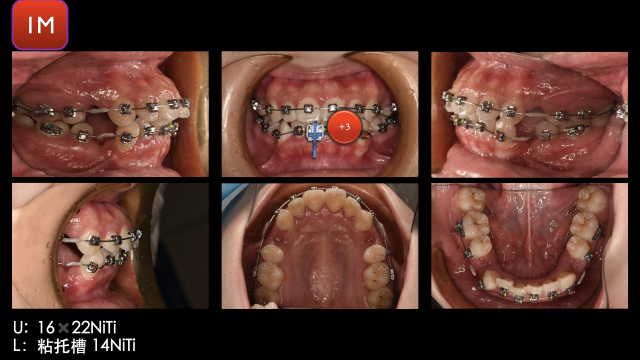

术前检查

术中治疗